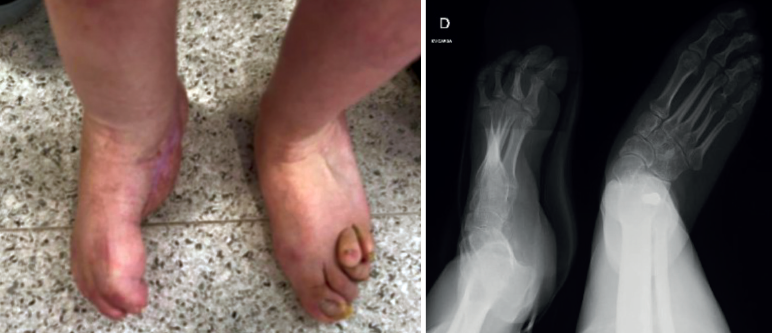

Sus dedos menores se encuentran en ráfaga media y presenta úlceras periódicas en la base de M5 por hiperapoyo (Figura 2). Además, la paciente nunca había tenido un pie plantígrado.

Figura 2. Pie derecho con apoyo en M5 y dedos en ráfaga medial. Radiografía en carga.

Cabe destacar que padeció una osteomielitis compleja en la base de M5 que requirió desbridamiento, tratamiento antifúngico y cobertura con colgajo de gracilis, por lo que su riesgo de infección era muy elevado.